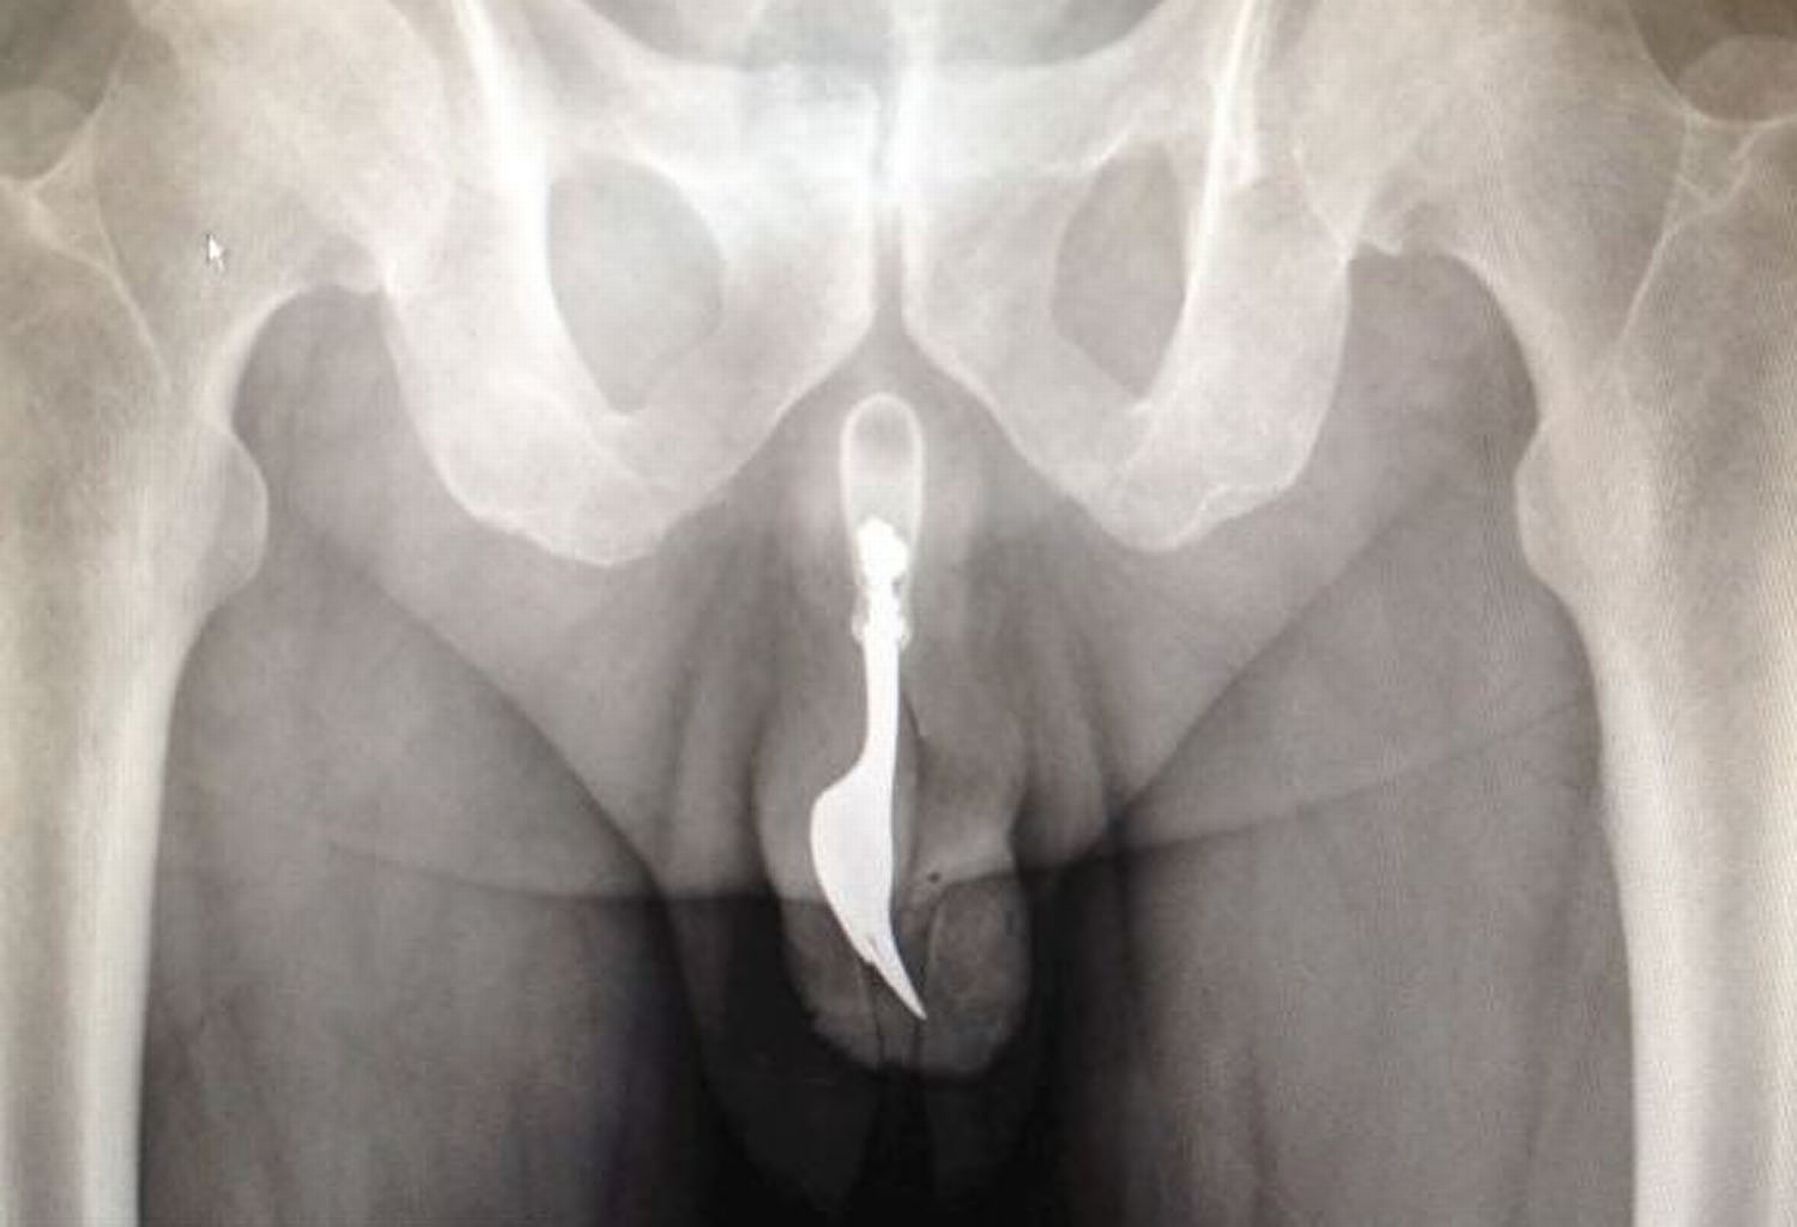

| Dĩa kim loại mắc kẹt trong dương vật một người đàn ông. |